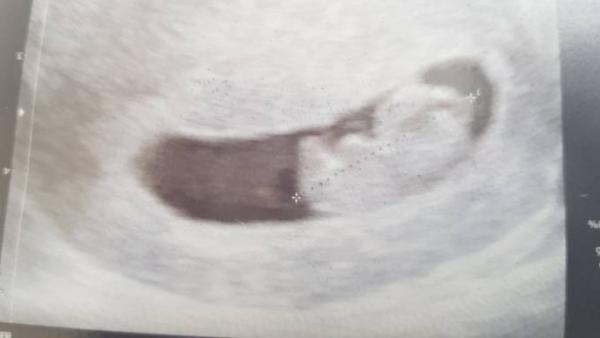

Hab mein Bild vergessen

Bild zu

Wahnsinn!!!!!! Wie groß das Bärchen schon ist Freut mich riesig das alles super war!!!!!!!!

Oh ja ich mich auch und zwar für uns alle. Ja es ist schon 4,1 cm. einfach nur der Wahnsinn.